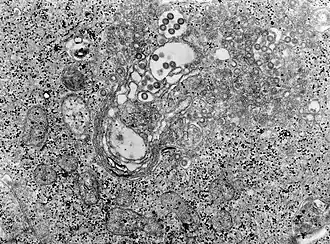

![]() Rift Valley: Фотография ткани под микроскопом инфицированной вирусом лихорадки | |